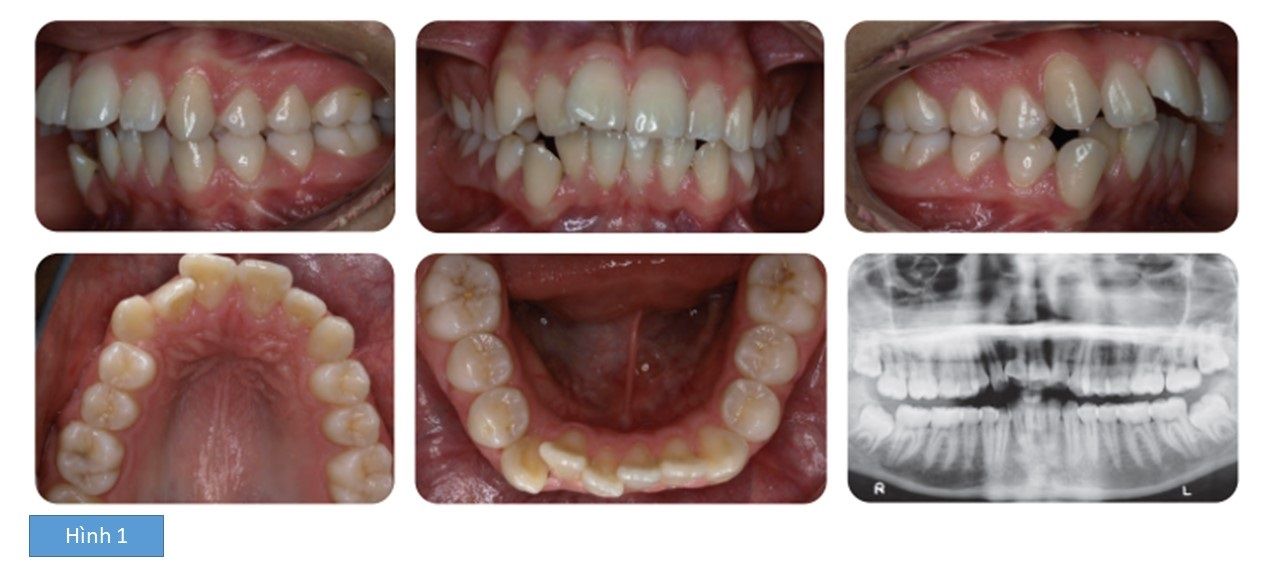

Bệnh nhân nữ 16 tuổi, băn khoăn về khe hở giữa các răng. Bệnh nhân bị sai lệch khớp cắn hạng II tiểu loại I trên nền xương loại II với kích thước dọc giảm, phức tạp bởi độ cắn chìa lớn (8mm), chen chúc cả 2 cung răng và hô 2 hàm (hình 1)